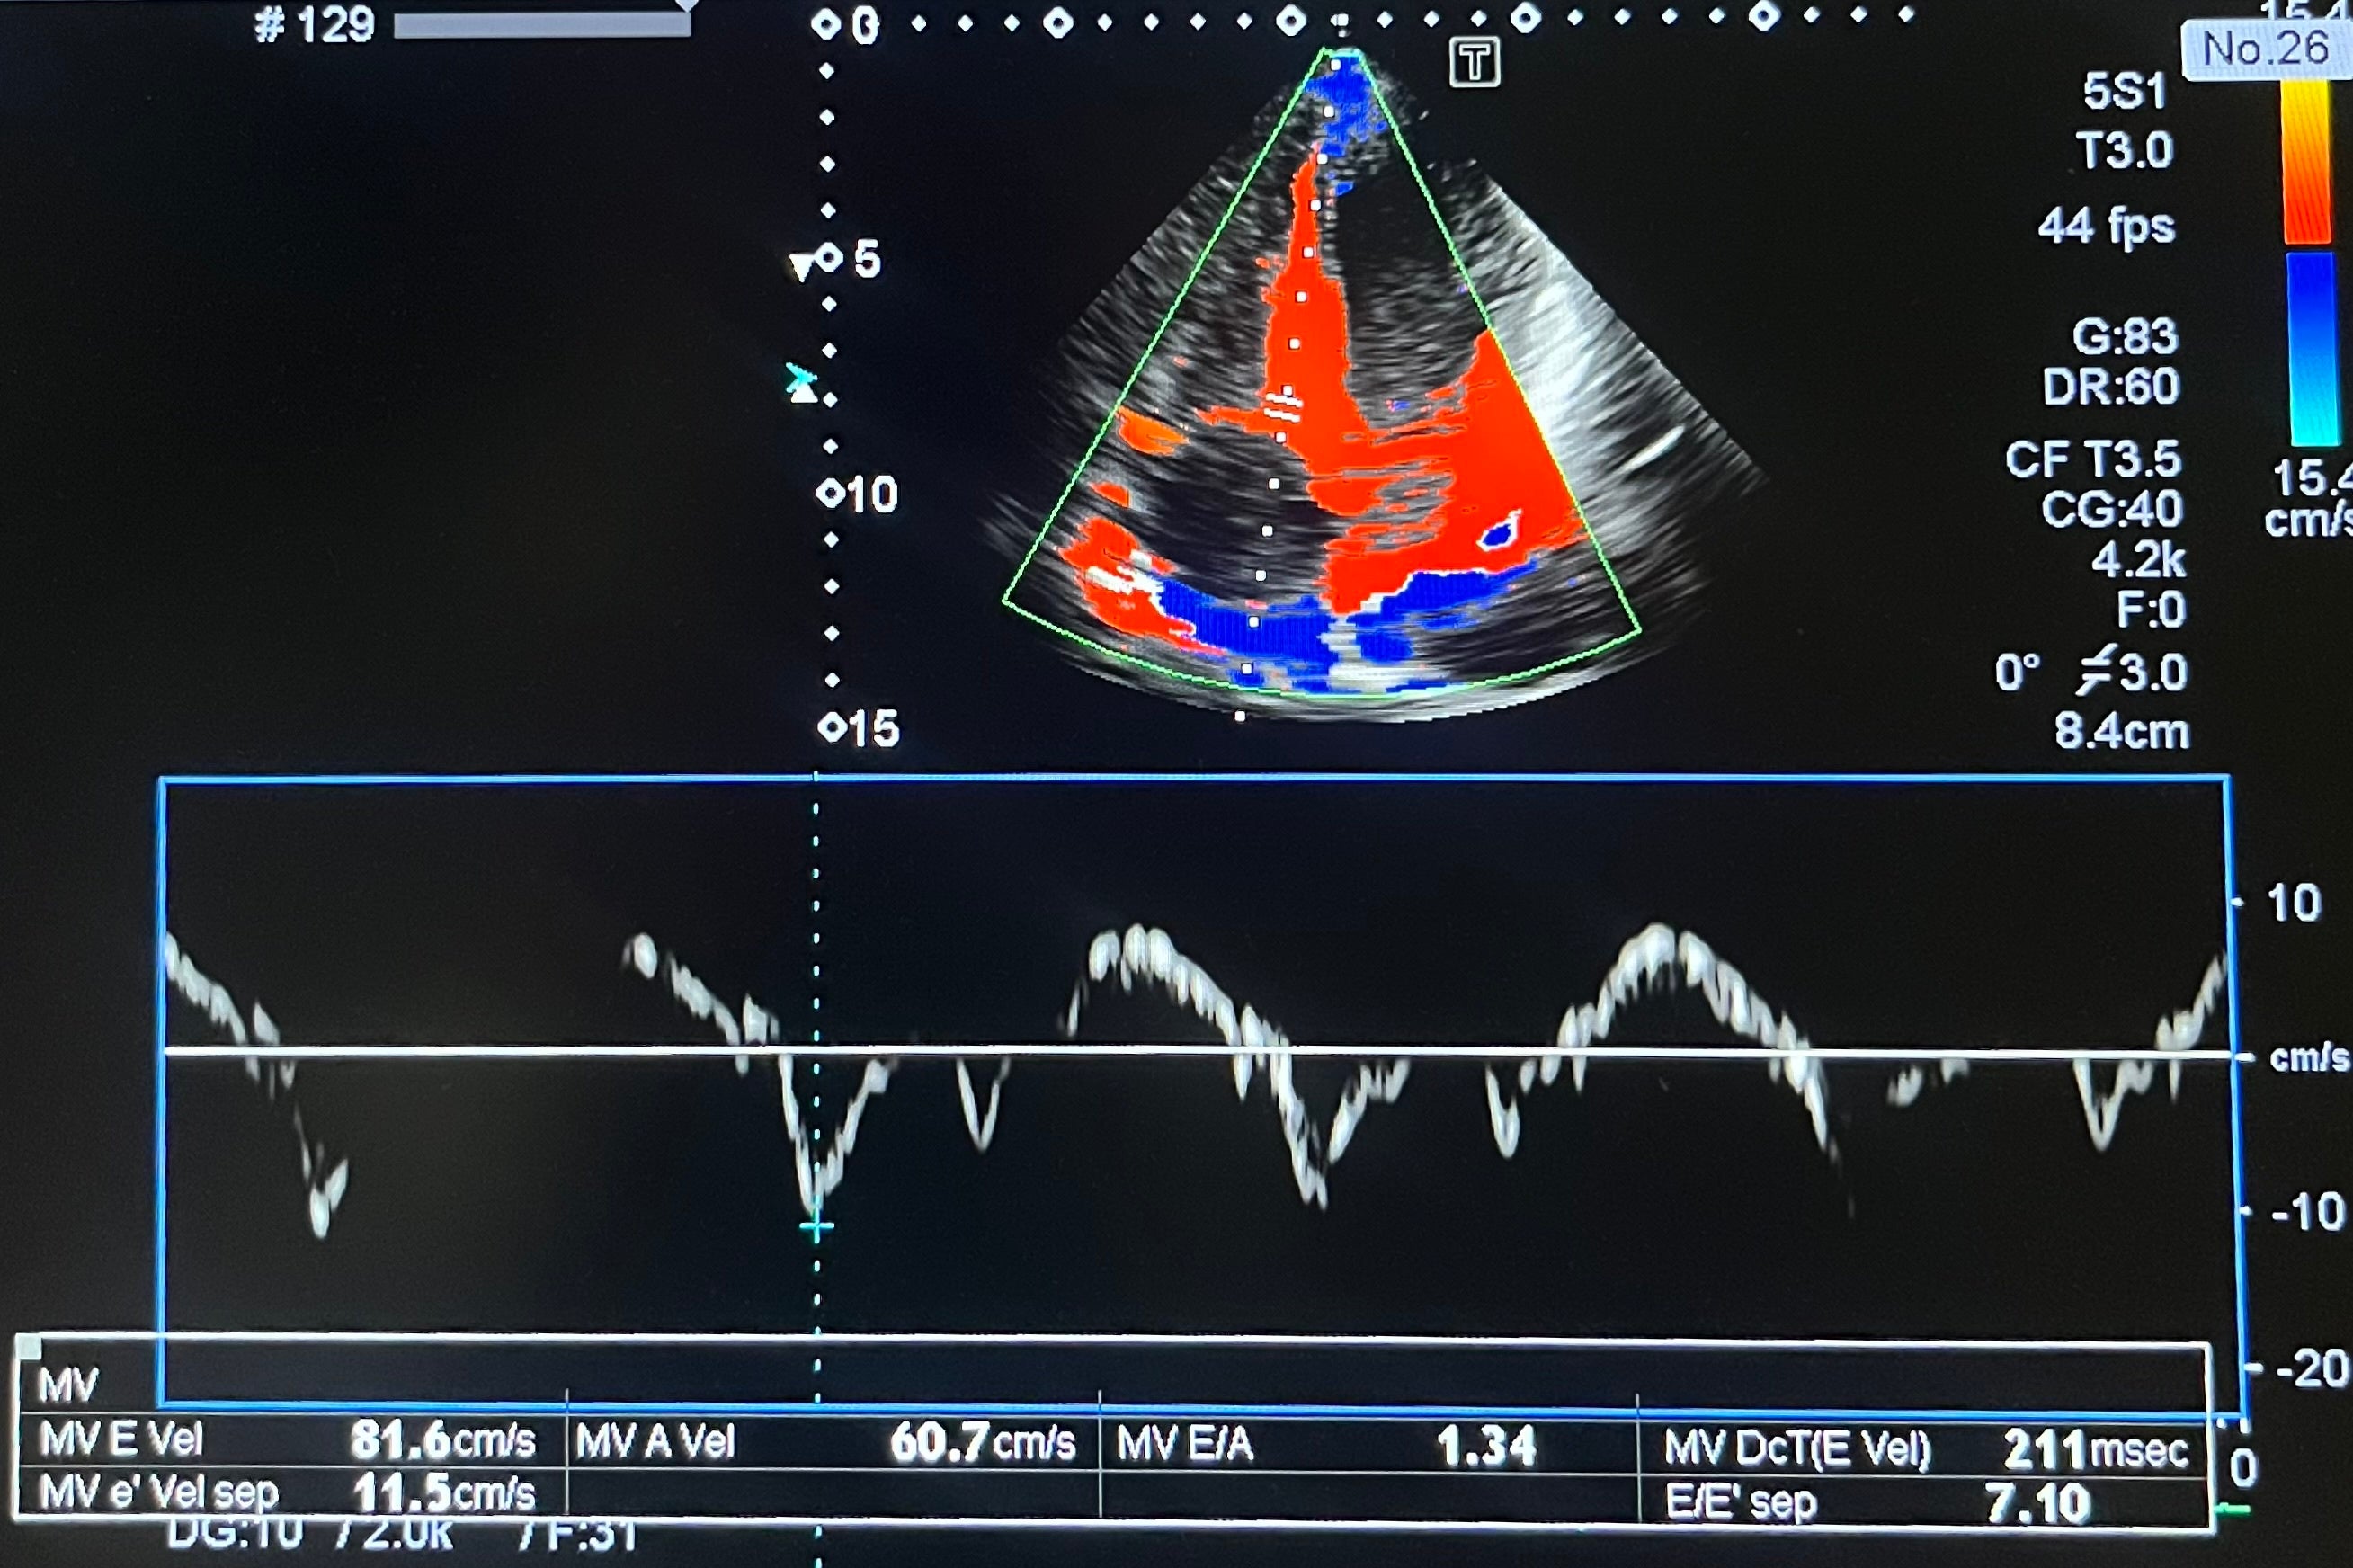

・心臓超音波

心臓の心房、心室の大きさや壁の厚さ、動きなど観察し、心肥大や心筋梗塞の範囲などを診断、心臓

の中の血液の流れ、弁の逆流がないか、弁の開閉が問題ないかも調べる事ができます。

心臓超音波画像